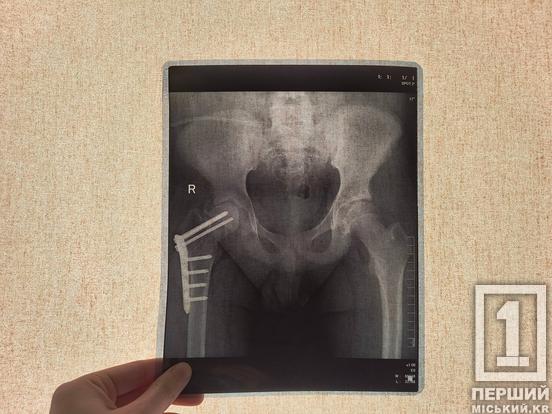

Перша операція у Дніпрі, де стегно зафіксували гвинтами, не дала бажаного результату. Через хворобу нирок кістки Андрія стали настільки крихкими, що метал почав мігрувати й руйнувати суглоб. Хлопець опинився на діалізі та прикутим до ліжка.

Під час надскладного втручання лікарі видалили старі шурупи та встановили фрагменти кістки у правильне положення. Але головною «фішкою» стала інноваційна регенеративна технологія. Прямо в лінію зламу Андрію ввели його власні стовбурові клітини, які перед цим відфільтрували з його ж жирової тканини. Вони мають стимулювати ріст кістки та допомогти організму самостійно «полагодити» пошкоджену ділянку.